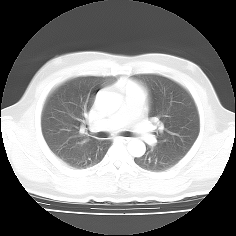

CTやMRIなどの医療機器によって生成されたスライスシリーズ画像を表示する場合、MPR(多断面再構成)表示法は、非常に有効な読影方法であり、特に任意角度の斜断面画像の再構成(Oblique)表示法は、臨床診断に非常に有用かつ重要な読影手法となっています。

ImageClarityのMPR表示機能は、エンジンレベルで実現したもので、任意空間原点と任意3D方向の断面を表示することが可能になっており、補正表示をしながら実用レベルの高速表示を実現し、3D処理開発キットとしても非常に利用しやすいAPIを提供しています。 MPR以外に、任意サイズのMIP(最大値投影)表示法もサポートしています。

MPR/MIP表示